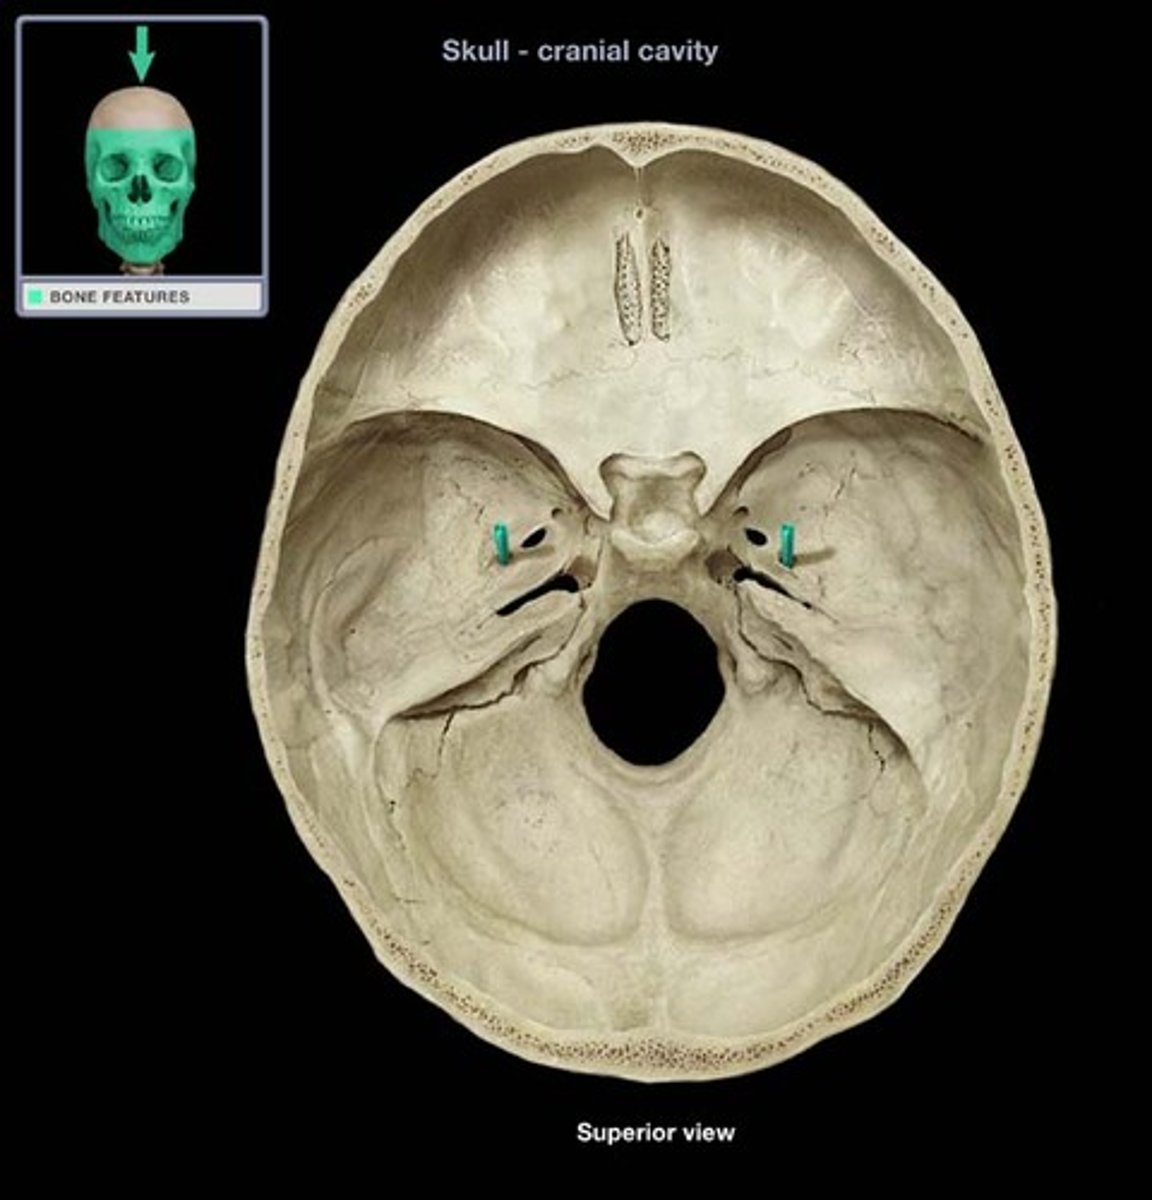

Foramen Magnum

The hole in the base of the skull through which the spinal cord passes

Hypoglossal Canal

Foramen in the occipital bone of the skull through which the hypoglossal nerve traverses

Foramen Lacerum

A triangular hole in the base of the skull located between the sphenoid, apex of petrous temporal and basilar part of occipital

Jugular Foramen

CN IX, X, XI, superior bulb of internal jugular, inferior petrosal and sigmoid sunuses, meningeal branches of ascending pharyngeal and occipital arteries pass through

Occipital Condyles

Rounded projections lateral to the foramen magnum that articulate with the first cervical vertebra (atlas)

Internal Acoustic Meatus

A passage for CN VIII from the inner ear to the brain

Stylomastoid Process

A rounded opening on the inferior surface of the petrous temporal bone, between the base of styloid and the mastoid process of the temporal bone. It transmits the facial nerve.

Carotid Canal

The passageway in the temporal bone through which the internal carotid artery enters the middle cranial fossa from the neck

Cribriform Plate

Superior surface of the ethmoid; perforated by a foramina which allows passage of the olfactory nerves, which provide sense of smell

Crista Galli

A thick, midline, smooth triangular process arising from the superior surface of the ethmoid bone, projecting into the anterior cranial fossa. Attaches to fall cerebri.